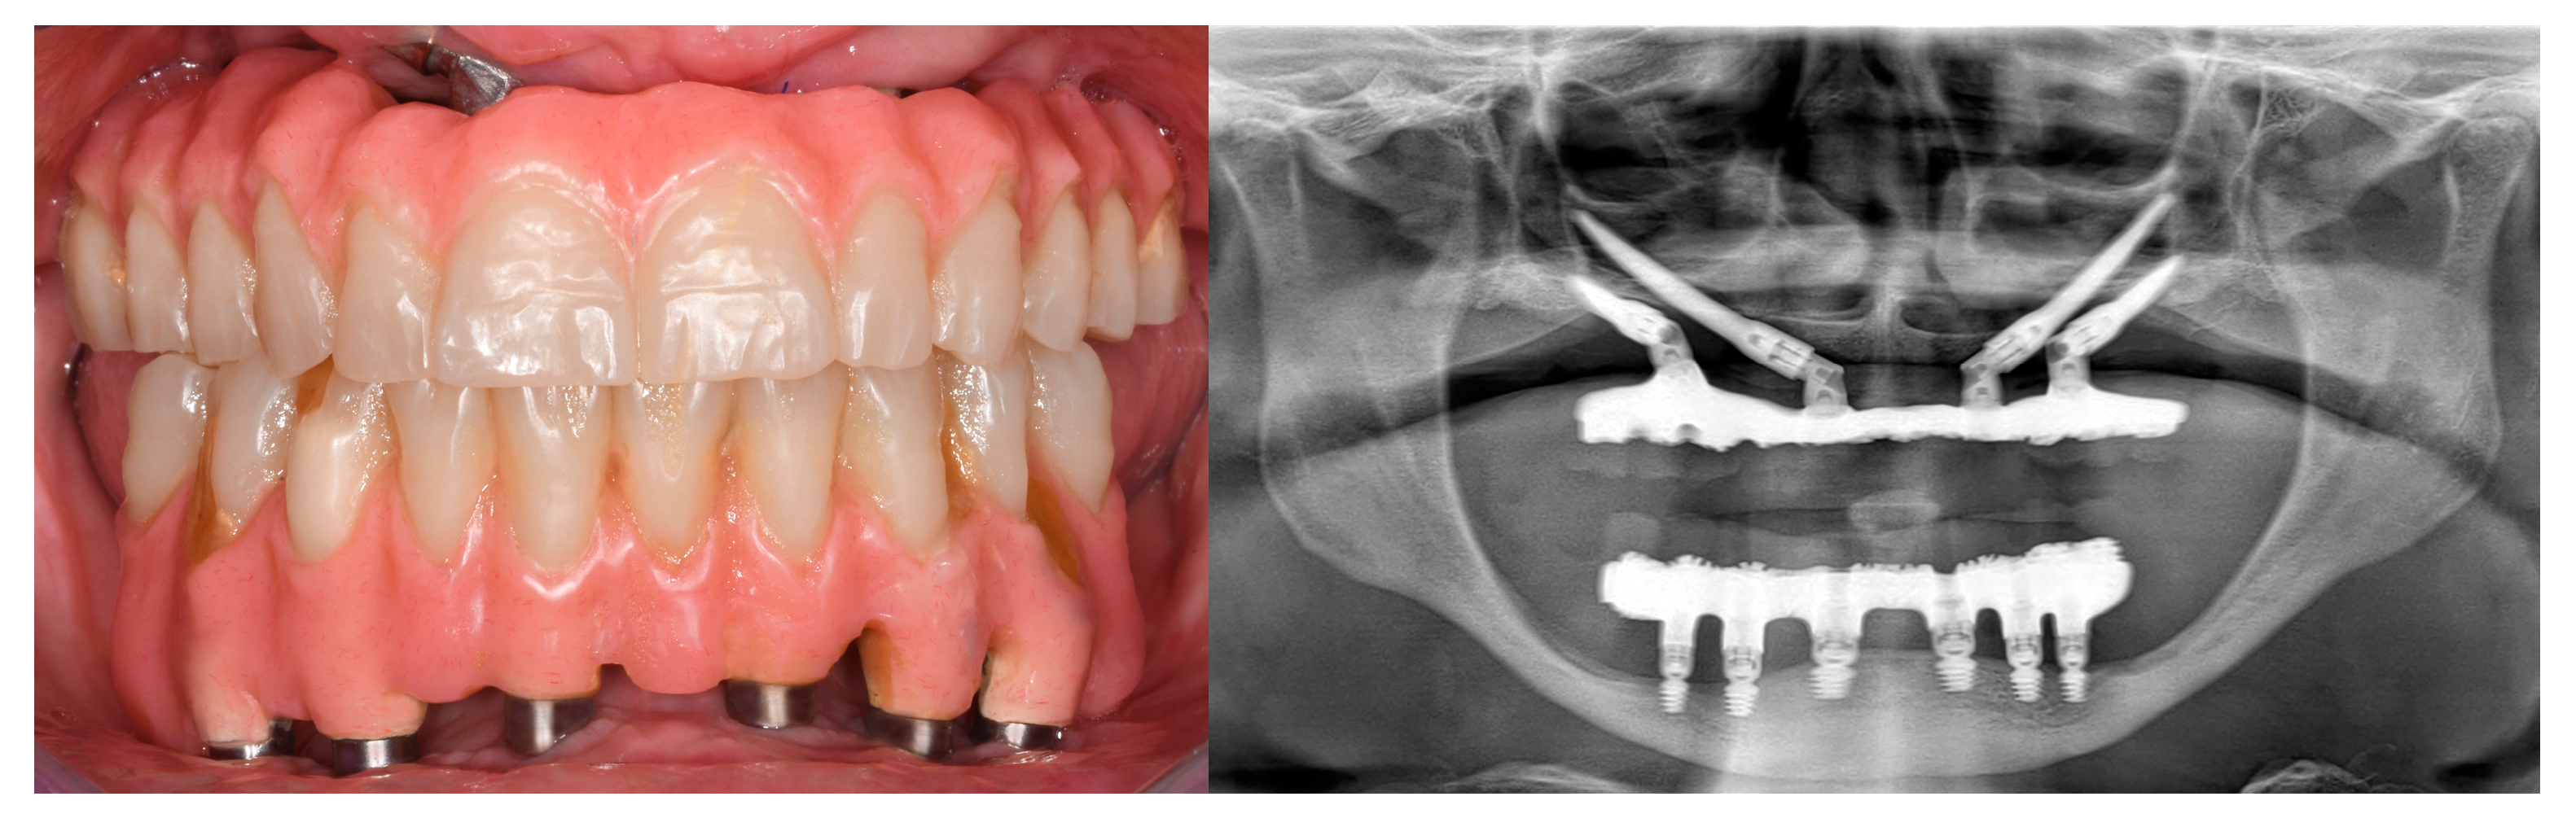

3.3. Fixed Full-Arch Prostheses